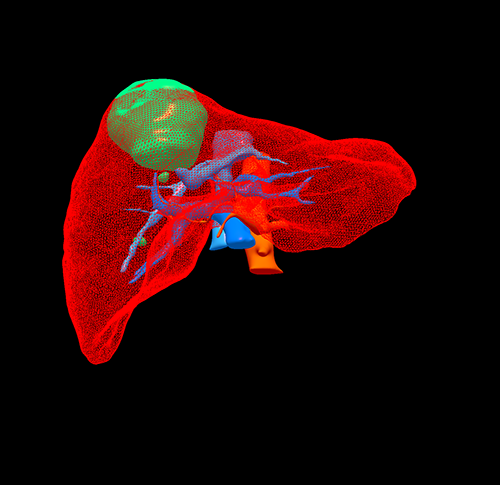

右肝癌---右三肝切除

介入后2周